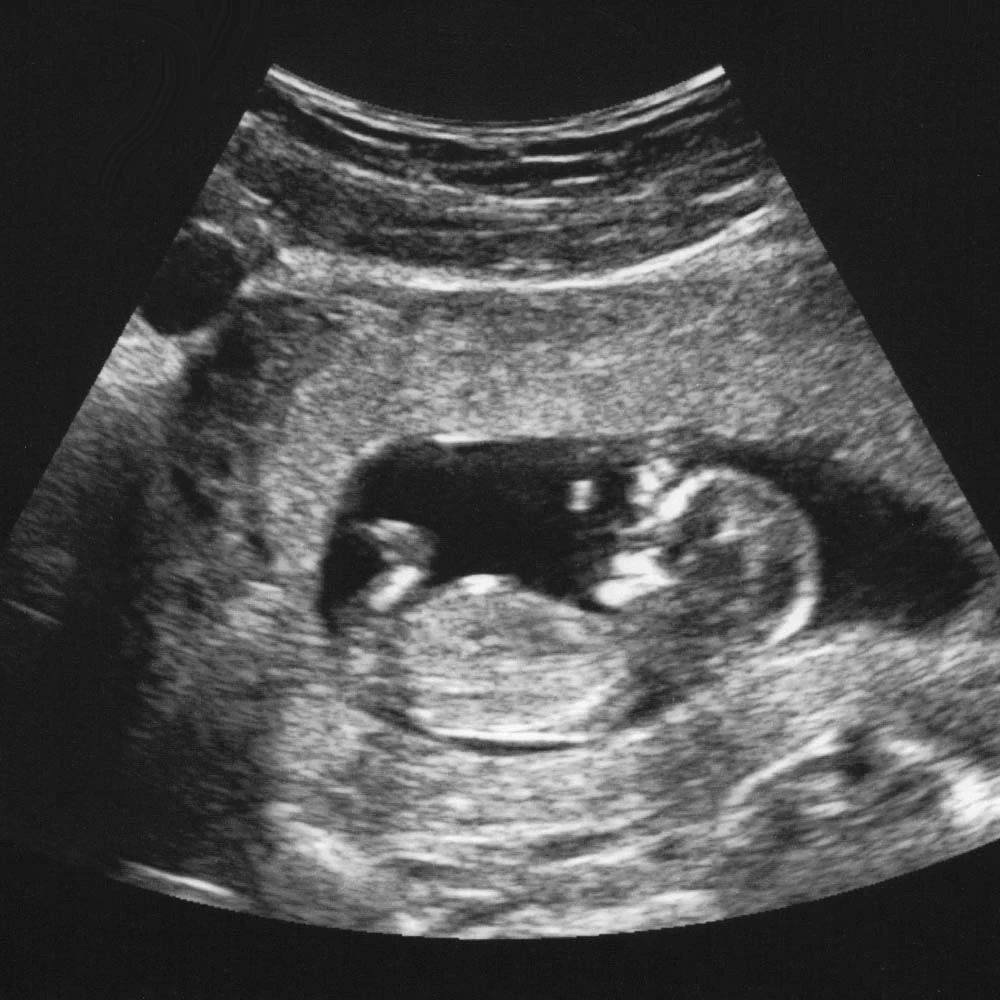

Неделя № 14

Копчиково-теменной размер к концу четырнадцатой недели увеличивается до 8-9 см. На лице хорошо очерчены лоб, нос, появляются щеки и подбородок. На голове появляются первые волосы (очень тонкие и бесцветные). Поверхность тела покрывается пушковыми волосками, которые удерживают смазку кожи и тем самым выполняют защитные функции.

Усиливается двигательная активность: плод может переворачиваться, изгибаться, совершать плавательные движения.

Почки начинают выделять мочу, которая смешивается с околоплодными водами.

Начинают работать клетки поджелудочной железы, вырабатывая инсулин, формируются клетки гипофиза.

На четырнадцатой неделе при хорошем чувствительном аппарате УЗИ уже можно определить пол ребенка.